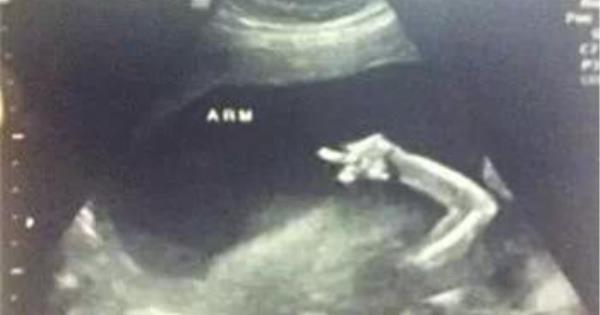

FUCK!說的別拍啦!

再拍我要揍你,信不信?!